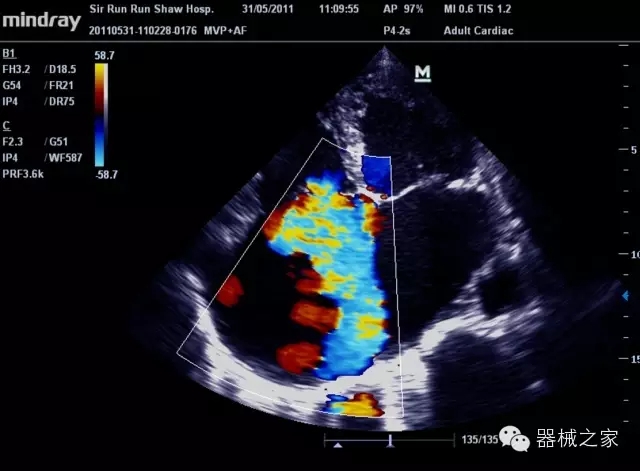

臨床圖片賞析

8倍波束并行處理系統(tǒng)

·在便攜式緊湊平臺(tái)上采用更多倍波束并行接收信號(hào)處理模式,無論二維還是彩色血流圖像狀態(tài)下,擁有更靈敏的回波頻移捕獲能力,大大提高時(shí)間分辨率,尤其使得心血管表現(xiàn)更為突出;